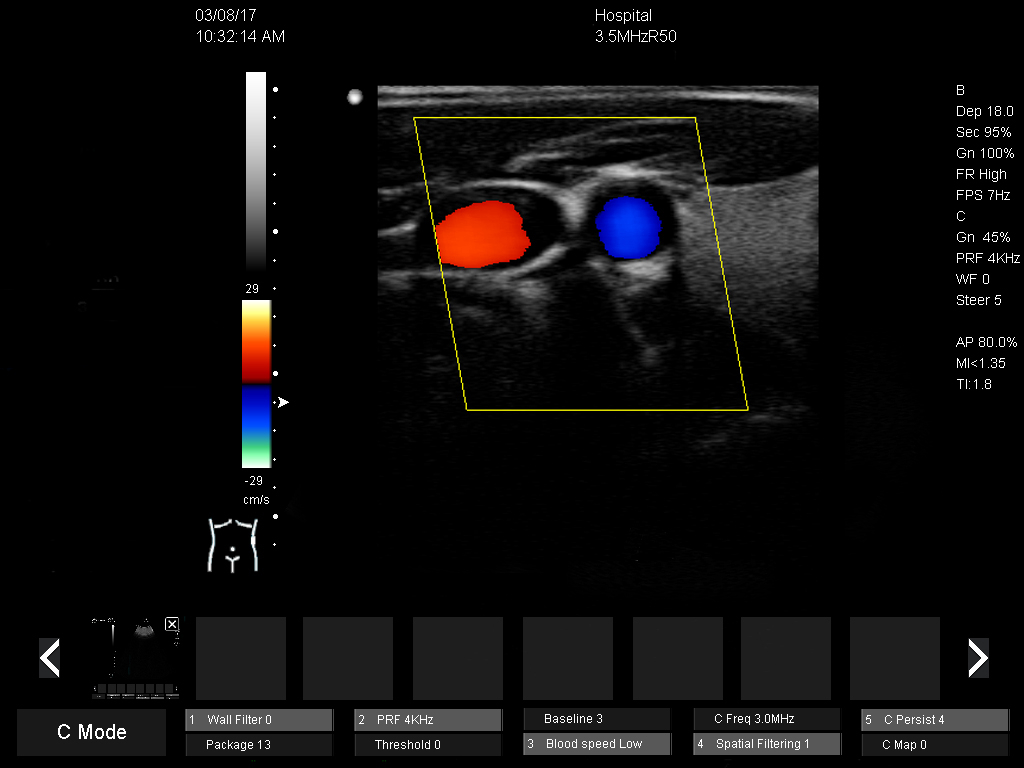

DMU51 Trolley Color Doppler Ultrasound Scanner Ultrasound Machine 3d/4d Color Doppler

6)Crystal clear 2D image and sensitive Color Doppler blood flow imaging system

1)Displaying mode:B,B/B,4B,B/M,M, B/C,B/C/D,B/D, duplex, triplex, CFM, PW,CW(optional), 4D(optional)

8)Vascular:Senosis D, senosis A, Intima, Arterial, Venous